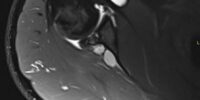

Resonancia magnética convencional y artro-resonancia

Estudios personalizados en equipos de alto campo magnético (1.5 y 3 Teslas) de articulaciones, columna, estructuras óseas, tejidos blandos, plexos y modelantes. Artro-resonancia con contraste guiado por ultrasonido o fluoroscopía.